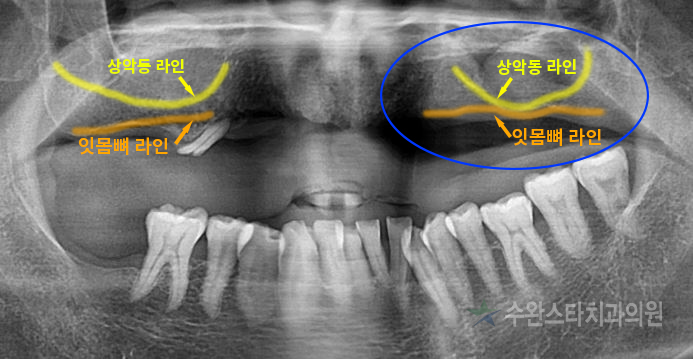

엑스레이 사진 중

파란색 동그라미로

표시한 부분을 보시면

노란색 상악동 라인과

주황색 잇몸뼈 라인이

거의 맞닿아 있는 모습을

볼 수 있습니다.

잔존 잇몸뼈가

거의 없다는 뜻입니다.